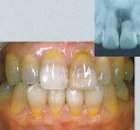

■CASE-2.(インプラント上部構造)

症例のような顕著な着色歯の場合も、Sinfonyは色を混和することで患者固有の色調を

忠実に再現することができます。

[術前] [アパッチメント装着] [術後]